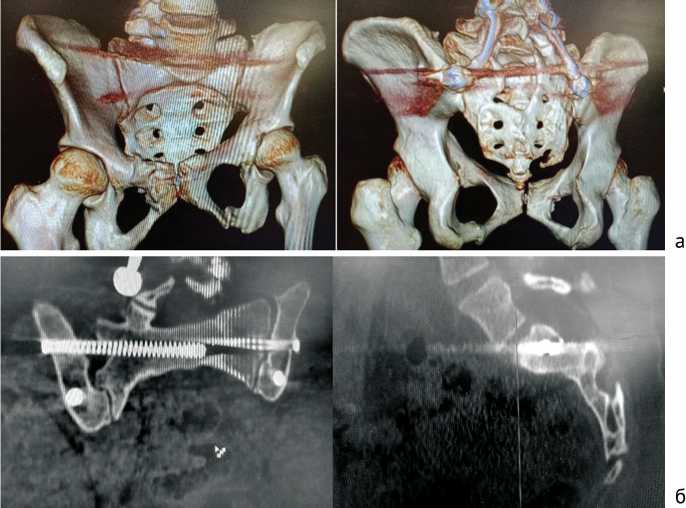

В положении на спине через два разреза кожи по 0,5 см в области лонного сочленения выполнен ретроградный малоинвазивный металлоостеосинтез перелома правой лонной кости канюлированным винтом диаметром 5 мм длиной 40 мм и перелома левой вертлужной впадины винтом 110 мм диаметром 6,5 мм. Наложены швы на кожу, асептические повязки. При полипроекционном рентгенологическом исследовании таза и крестца определено удовлетворительное стояние отломков (рис. 3). Длительность операции — 4 ч. 20 мин., кровопотеря — 700 мл.

Рис. 3. Обзорные рентгенограммы таза после окончательного остеосинтеза: внутренние косая и прямая; наружная косая

Результат более 85 баллов по шкале Majeed (международная шкала отдаленных результатов хирургического лечения нестабильных повреждений костей таза и крестца) является отличным. Мы планируем удалить металлоконструкции. На компьютерных томограммах таза через шесть (рис. 5) и 12 мес. после операции (рис. 6) определяли консолидацию переломов таза и крестца, металлоконструкции стабильны.

Рис. 5. Компьютерные томограммы таза, шесть месяцев после операции: а — 3D-реконструкции

Рис. 5 (продолжение). Компьютерные томограммы таза, шесть месяцев после операции: б — сканы во фронтальной и сагиттальной проекциях